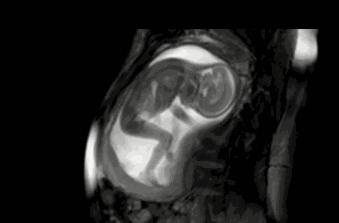

咦?这地儿怎么越来越小了,不管,我挤,我顶......

顶了这么久,“房子”怎么还是这么小?

管他呢,我要出去,我要游泳,我继续蹬腿,我蹬……

哇,看到没有!我的大长腿是不是很迷人!